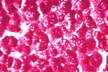

Alpha-1- antitrypsin

globules diastase PAS stain

( from College of

Amer. Pathologists)

Fig 30 - ALPHA-1-ANTITRYPSIN STORAGE: The periportal hepatocytes contain very visible citoplasmic inclusions that are diastase resistant PAS positive and can be identified with immunoperoxidase method as alpa-1-antitrypsin (A1AT) material. Diastase -PAS stain should be done routinely in liver biopsies. The inclusions are almost always present in homozygous (ZZ) or heterozygous (MZ,SZ) phenotypes of A1AT deficiency cases. Non-alpha-1-antitrypsin similar inclusions are occasinally seen in other conditions,such as:post mortem material and biopsy material in cirrhosis. Immunoperoxidase reaction for A1AT will solve the problem. Fibrinogen storage also may mimic A1AT inclusions.It can be detected with immunoperoxidase reaction.